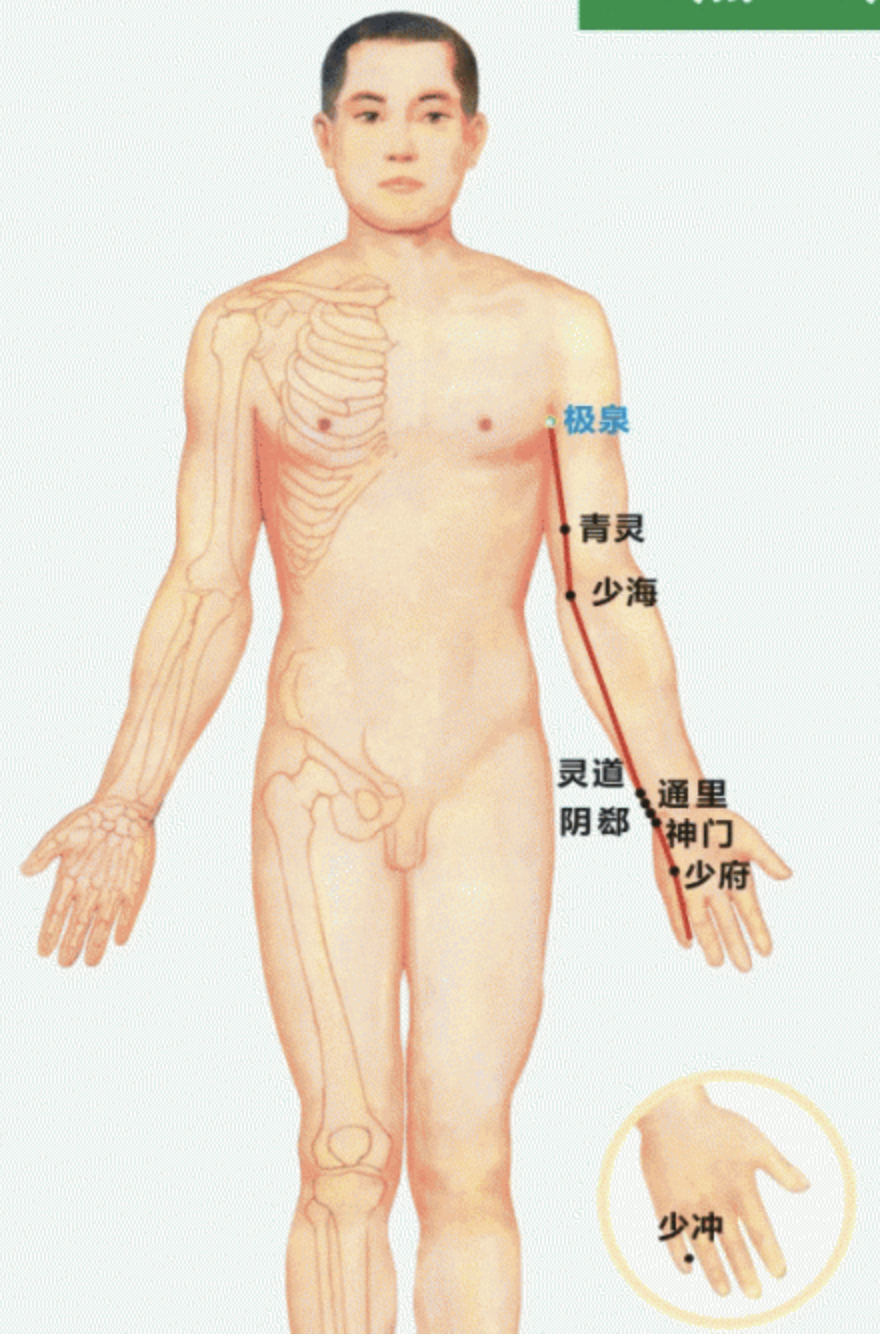

【(五)手少阴心经(图10-23-1)】

2、歌诀 手少阴心起极泉,青灵少海灵道全,通里阴郗(chī)神门下,少府少冲小指边。

3、经脉循行 起于心中,出属心系(心与其他脏器相连的部位),过膈,联络小肠。“心系”向上支脉:夹咽喉上行,连于目系(眼球连于脑的部位)。

“心系”直行的脉:上行于肺部再向下出于腋窝部(极泉),沿上臂内侧后缘,行于手太阴和手厥阴经的后面,至掌后腕豆骨部入掌内,沿小指内侧至末端(少冲)交于手太阳小肠经。

4、主要病候 心痛、咽干、口渴、目黄、胁痛、上臂内侧痛、手心发热等。

5、主治概要 主治心、胸、神志病及经脉循行部位的其他病证。